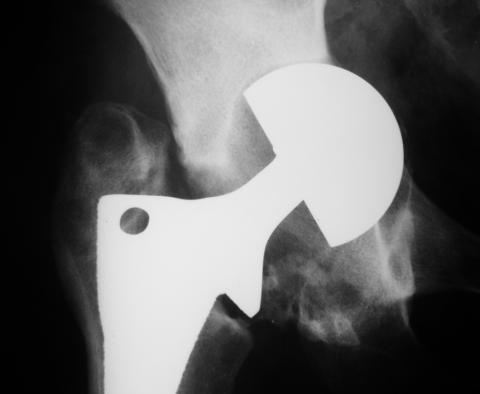

Уважаемые коллеги!молодой человек 22 лет обратился к нам с жалобами на умеренную боль в в/3 левого бедра и паху при ходьбе, укорочение левой ноги. 3 года назад получил закрытый перелом шейки левого бедра (рис 1).

Лечился в стержневом аппарате по месту жительства. АВФ демонтировали через полгода из-за воспаления в области стержней (рис 2). После демонтажа в течение месяца больной лихорадил до 38*, были боли в бедре. Эти явления исчезли после курса антибиотиков. Через год после травмы в ЦРБ ему имплантировали биполярный протез (рис 3). Рана зажила первично. Ходил с костылями, слегка приступая на ногу. На контрольных осмотрах выявлена прогрессирующая протрузия (рис 4-6).